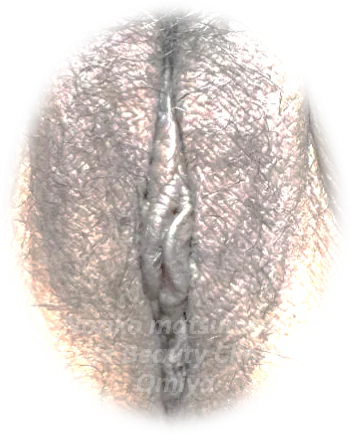

【#2-1】【他院修正】左副皮+左小陰唇縮小

術前

デザイン

術後1ヶ月| 施術内容 |

【他院修正】左副皮+左小陰唇縮小(副皮の余り、小陰唇の不整な形を修正希望) |

この方は、「もう少し副皮を切りたい」というご要望でした。わずかな変化ですが、小陰唇のギザギザとした部分も修正しています。 |